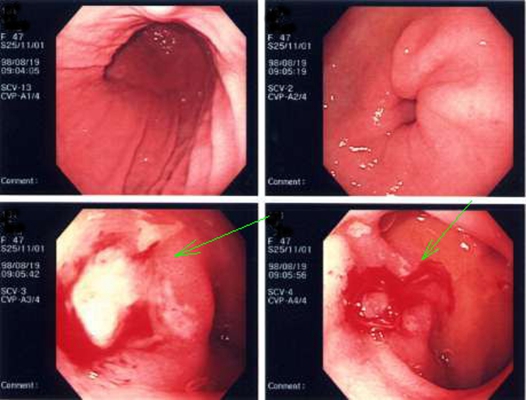

食道炎圖片